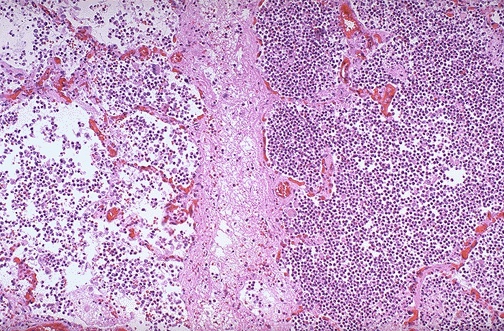

Image 3.6

The microscopic appearance of an area of consolidation is seen here at medium power.